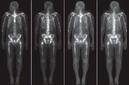

İskelet Nedir? İskelet Özellikleri ve Faydaları Nelerdir?